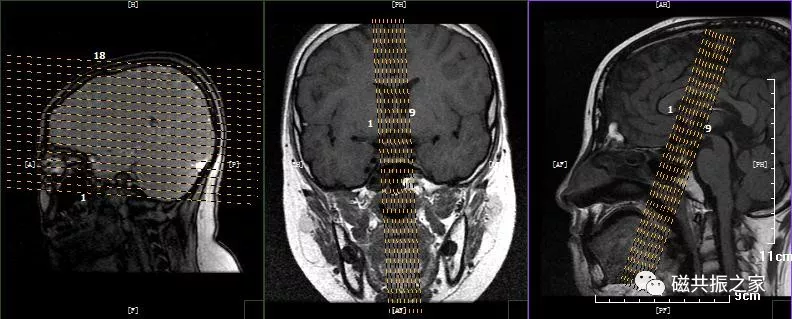

冠状位:CORDynamicT1FSE冠状位T1多期动态增强序列

以矢状位和横断位作为参考定位。定位方法同上面的平扫序列,双侧对称扫描,扫描范围包括整个垂体,为了保证时间分辨率,扫描层数不宜过多,5-7层。注射对比剂前先扫描一期蒙片,暂停,然后注射对比剂的同时开始连续的动态扫描(1.5T:8-10期,每一期20S左右最佳,3.0T:15-20期,每期10S左右最佳),整个动态增强序列扫描3min左右即可。

动态增强通常采用冠状面扫描。注射对比剂前扫描一期蒙片的目的:评估扫描所得的图像质量是否能满足诊断要求,包括范围、信噪比,伪影等。

为了保证足够的信噪比应适当的加大FOV,减小矩阵。

不使用饱和带,可缩短扫描时间。

为了保证时间分辨率扫描层数不宜过多,回波链可适当加长(可以加到5)。

造影剂采用半剂量:0.1ml/kg或者0.05mmol/kg,速率2-3ml/s。

注射对比剂的同时开始连续的动态增强扫描;也有采用注射对比剂后延迟5s后,再开始扫描的,这两种扫描方式均可。